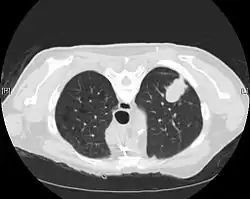

CT scan- adenocarcinoma of the left lung

The majority of lung cancers can be characterized as either small cell lung cancer (SCLC) or non-small cell lung cancer (NSCLC). Lung adenocarcinoma is one of the three major subtypes of NSCLC, which also include squamous carcinoma and large cell carcinoma.[15]

Imaging

CT imaging provides better evaluation of the lungs, with higher sensitivity and specificity for lung cancer compared to chest radiograph (although still significant false positive rate[27]). Computed tomography (CT) that is specifically aimed at evaluating lung cancer includes the chest and the upper abdomen. This allows for evaluation of other relevant anatomic structures such as nearby lymph nodes, adrenal glands, liver, and bones which may show evidence of metastatic spread of disease.[4] Indeed, the US Preventative Services Task Force recommends annual screening with low-dose CT in adults aged 55 to 80 years who have a 30 pack-year smoking history and currently smoke or have quit within the past 15 years, with certain caveats (see Lung cancer screening).[28]

Nuclear medicine imaging, such as PET/CT and bone scan, may also be helpful to diagnose and detect metastatic disease elsewhere in the body.[7] PET/CT uses a metabolically active tracer that allows clinicians to identify areas of the body that are hypermetabolic. Increased uptake of the tracer occurs in malignant cells and areas of inflammation or infection. Integrating the imaging reflective of metabolic activity with normal CT imaging allows for higher sensitivity and specificity compared to PET alone.[4]

MRI is reserved for patients with advanced disease where intracranial, or brain, involvement is likely. It is also helpful for evaluating the extent of chest wall, diaphragmatic, brachial plexus (such as in the case of superior sulcus tumors), or spine involvement.[4]